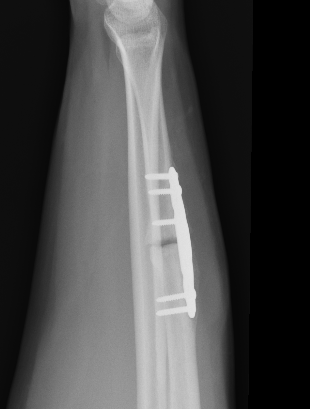

Compression plating

Intra-medullary nail

Ulna Intramedullary WireUlna Plating

Technique

AO foundation ulna plating